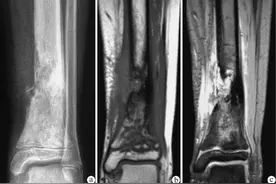

近期碰到一个特殊的病例(图1),一个“左小腿肿痛,X线显示胫骨干皮质增厚,髓腔狭窄”的病人,在进行教学病例讨论的过程中,有老师提出,胫骨硬化性骨髓炎的可能。当时在现场我就蒙了。骨髓炎?在我的印象中,我见过“红肿热痛”的急性骨髓炎,也遇到过“骨质破坏,死骨形成”的慢性骨髓炎。但是硬化性骨髓炎是什么东西啊?上网一查,原来真有这种类型。于是怀着对知识的渴望,查阅骨科书籍以及检索中英文文献,介绍一下骨髓炎的特殊类型,希望通过今天的学习,对硬化性骨髓炎有个更深刻的认识,避免临床上的误诊,漏诊。

图1